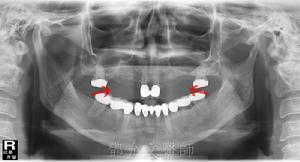

5.恆牙列中任何一顆牙都有先天缺失的可能,最常見為第三磨牙,其次為下頜第二前磨牙、6.上頜側切牙和上頜第二前磨牙。最少缺失的是第一磨牙,其次是第二磨牙。

7.缺磨牙的患者多伴有其他牙齒的缺失,單純缺磨牙者少。

8.牙齒缺失可發生在單側也可發生在雙側。

9.缺失牙位多呈對稱性分布。